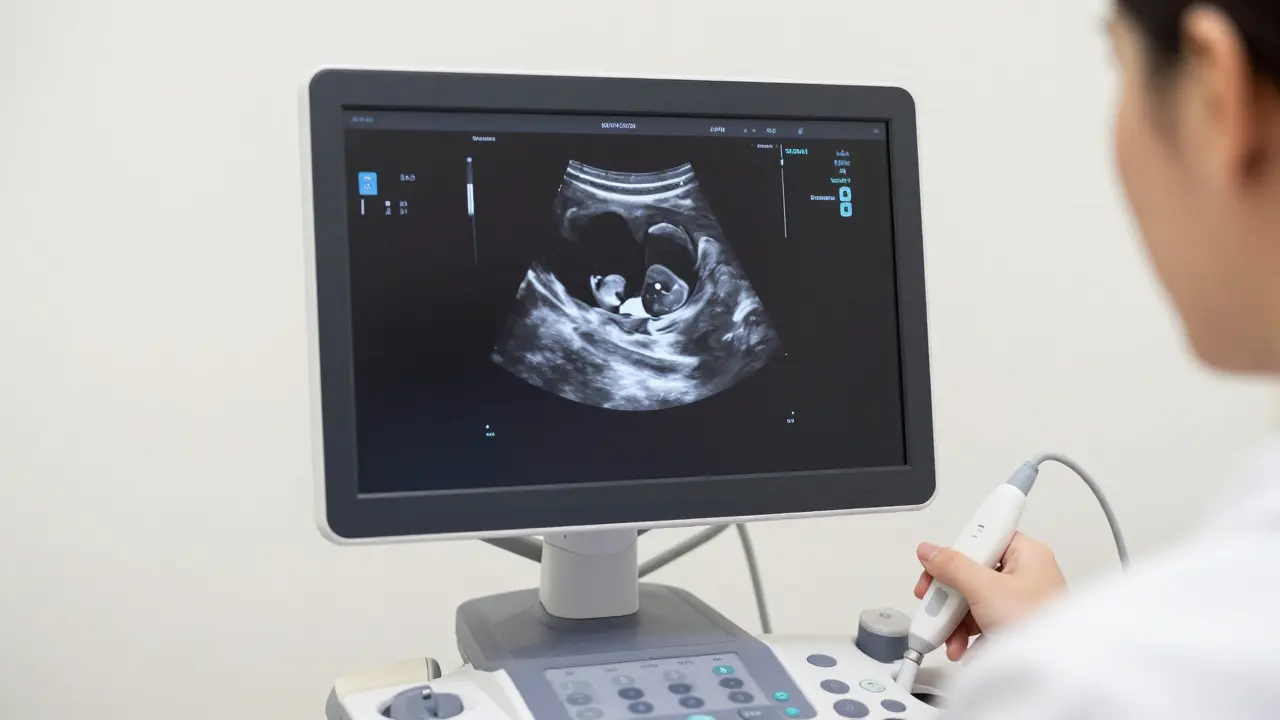

Většina lékařů doporučuje první návštěvu kolem 6. až 8. týdne těhotenství. Proč ne dříve? Protože v 4. nebo 5. týdnu je první ultrazvuk v těhotenství je diagnostické vyšetření pomocí vysokofrekvenčních zvukových vln, které umožňuje vizualizaci plodu a potvrzení správného umístění vajíčka v děloze často neinformativní. V té době je embryo tak malé, že ho přístroj prostě nesrazí. Budete sice vidět zahuštěnou sliznici, ale žádné tlukání srdce ani jasnou strukturu plodu.

Kolem 6. týdne už je situace jiná. Embryo je dost velké na to, aby bylo vidět jako malá tečka, a co je nejdůležitější - můžete slyšet nebo vidět první tlukání srdíčka. To je ten moment, kdy se z "podezření na těhotenství" stává potvrzené těhotenství. Pokud jste sice v Praze a hledáte moderní gynekologie Praha s nejnovějším vybavením, pamatujte, že i nejlepší přístroje mají své fyzikální limity. Příliš brzký spěch může vést k falešnému stresu, pokud lékař nic nenajde, ačkoliv je vše v pořádku.

Možná vás překvapí, že vás lékař v prvních týdnech dopustí k vyšetření "zespodu". Transvaginalní ultrazvuk (pomocí sondy zaváděné do pochvy) je v tomto stadium mnohem přesnější. Protože je sonda fyzicky blíže k děloze, obraz je mnohem ostřejší a detaily jsou vidět dříve. Abdominální ultrazvuk, tedy ten přes břicho, se začne běžně používat až později, kdy plod naroste a děloha vyjde z malého pánvového prostoru.

Je to trochu nepohodlné, ale je to nejrychlejší cesta k odpovědi na otázku, zda je vše v pořádku. Uvnitř dělohy hledá lékař především gestacionální vakule, což je takový "bublík", ve kterém se embryo vyvíjí. Pokud je vakule na správném místě a v ní vidíme embryo s tlukotem, můžete vydechnout.